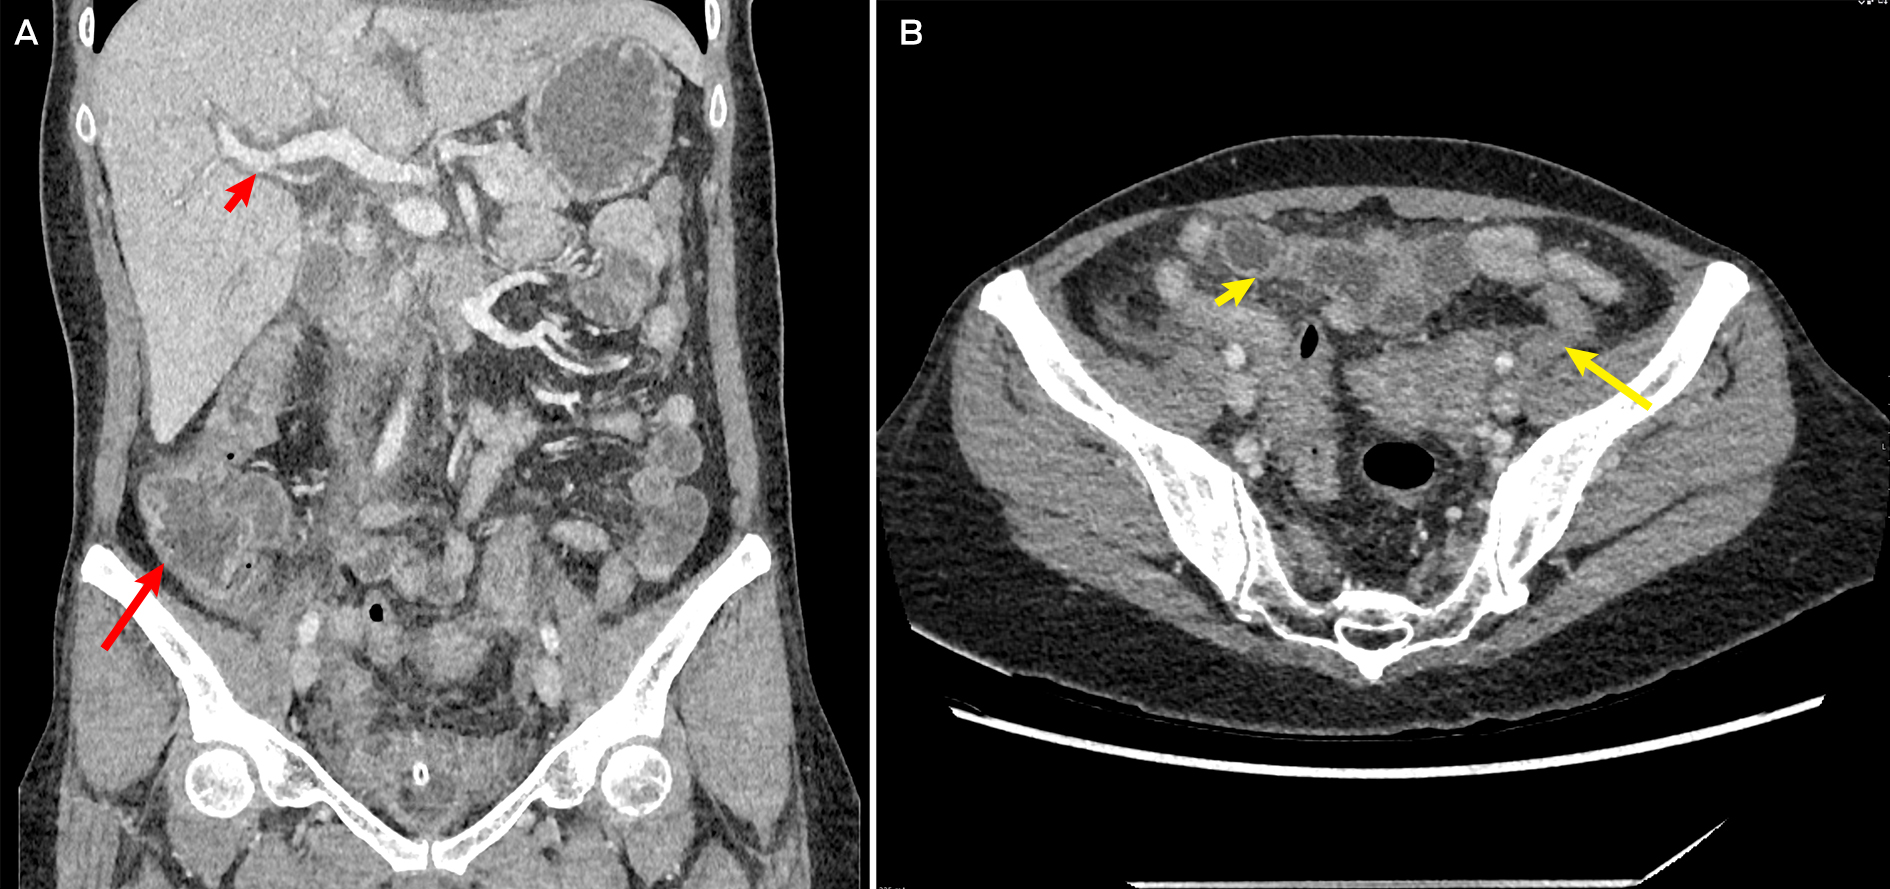

Initial investigations revealed an acute kidney injury (serum creatinine, 261 μmol/L; reference interval [RI], 45–90 μmol/L; baseline unknown but reportedly normal); mild transaminitis (alanine transaminase, 67 U/L [RI, 10–35U/L]; aspartate aminotransferase, 51 U/L [RI, 10–35 U/L]); neutrophilic leucocytosis (neutrophil count, 16.9 × 109/L [RI, 2–7 × 109/L]); and an elevated C‐reactive protein level of 423.4 mg/L (RI, ≤ 4.9 mg/L). The patient's lactate level was normal (1.9 mmol/L [RI ≤ 1.9mmol/L]). Computed tomography (abdomen and pelvis) showed severe pancolitis, with diffuse mural thickening from the ascending colon to the rectum, and trace free fluid in the pelvis (Box).

Box – Computed tomography of the abdomen showing pancolitis

A: Representative coronal slice showing prominent caecal and ascending colon mural thickening (long arrow) and periportal thickening (short arrow), suggestive of pancolitis. B: Axial slice showing prominent sigmoid (long arrow) and transverse colon (short arrow) mural thickening, consistent with overall diagnosis of pancolitis.